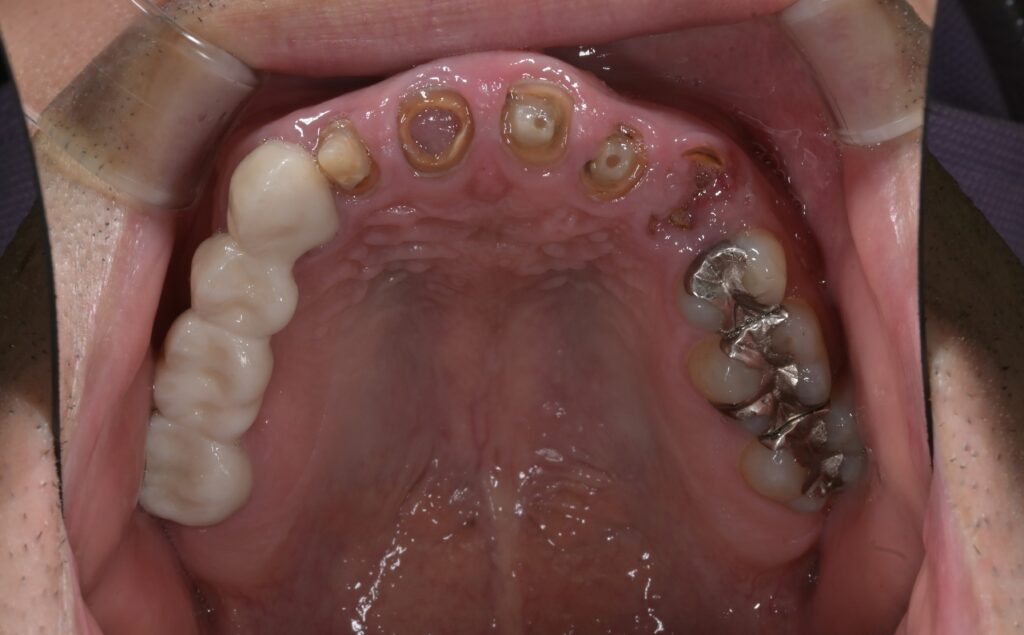

多くの治療が必要な患者さんの場合、当院でお願いしていることは、歯科治療の優先順位を上げて欲しいことです。

大がかりに治療しなければならない方、多くの歯の治療がある方は、やはり、歯科治療に時間を確保する必要性があるのです。